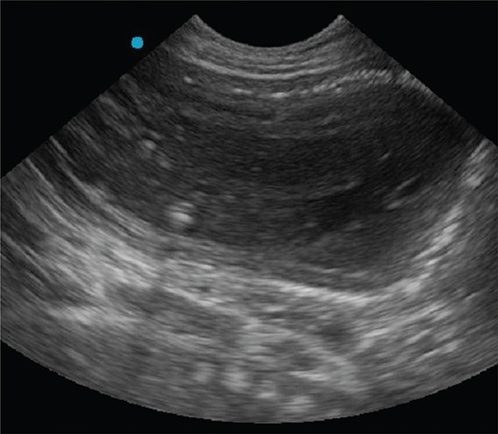

Physical examination findings were underweight (body condition score of 3/9 [Royal Canin© scale])4 and a moderate amount of nonfetid dark brown vulvar discharge. A large number of fetuses (fetal heart rates ranged between 200 and 250/beats per minute [bpm]) were observed via focal transabdominal ultrasonography. Serum progesterone concentration was 1.25 ng/ml. Bloodwork findings included mild normocytic normochromic anemia (categorized regenerative due to anisocytosis and polychromasia), mild monocytosis, mild hypocalcemia, and mild hyponatremia. Additional tests included leptospirosis witness test (WITNESS® Lepto, Zoetis, Parsippany, NJ), Brucella canis rapid slide agglutination test (D-TEC® CB, Zoetis), canine herpesvirus titer (Colorado State University, Fort Collins, CO), and SNAP 4Dx testing (anaplasma, ehrlichia, Lyme, and heartworm) (SNAP® 4Dx Plus Test, Idexx, Westbrook, ME); all were negative. Ten premature fetuses were counted (abdominal radiography), and their immaturity was determined based on the level of calcification, without evidence of fetal death (Figure 1). An immediate cesarean surgery with ovariohysterectomy was recommended but was declined by the owner. As the patient appeared stable, outpatient therapy was discussed initially; however, another fetus aborted necessitating overnight hospitalization. Therapies included intravenous lactated Ringer’s solution (90 ml/kg/day [Excel®, B. Braun Medical Inc., Bethlehem, PA]), subcutaneous terbutaline (0.03 mg/kg three times a day [Brethine®, Hikma Pharmaceuticals PLC, London, United Kingdom]), oral altrenogest (0.088 mg/kg once a day [Regu-Mate®, Merck Animal Health, Rahway, NJ]), oral amoxicillin and clavulanate potassium (14 mg/kg twice a day [Clavamox®, Zoetis, Parsippany, NJ]), oral clindamycin (11.8 mg/kg twice a day [Cleocin®, Lannett Company, Inc., Philadelphia, PA]), and oral fenbendazole (50 mg/kg once a day for 3 days [Panacur®, Merck Animal Health, Rahway, NJ]). Both aborted fetuses were submitted for necropsy, and were premature (lack of hair growth).

Fig. 1.

Figure 1. Right lateral abdominal radiograph (50 days after breeding), note the 10 fetuses and poor calcification (immaturity).